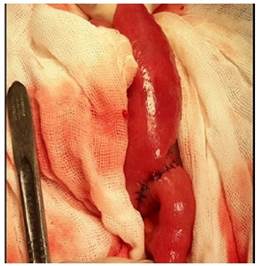

El procedimiento se realiza bajo anestesia general, paciente en posición decúbito dorsal, se decide realizar una incisión en línea media supra e infraumbilical, se procede a explorar cavidad, se localiza sitio de obstrucción a 50 cm de ángulo de Treizt; los hallazgos demuestran un cálculo de más o menos 4 x 5 cm impactado en yeyuno, a 50 cm de ángulo de Treizt, asas intestinales dilatadas a proximal; se realiza una laparotomía exploradora, enterotomía, extracción de cálculo, enterorrafia, lavado y drenaje de cavidad. Diagnostico post operatorio de obstrucción intestinal alta, Ileo biliar, Síndrome de Mirizzi grado Vb (Figura 3a, b, c d).

Existe una controversia en cuanto al manejo de la fístula bilioentérica; en un primer tiempo o dos tiempos14. Por un lado, se prefiere sólo la enterotomía, extracción del lito y cierre primario, y por otro, además de lo anterior, se realiza desmantelamiento de la fístula y colecistectomía13),(15. En nuestro caso, decidimos realizar únicamente enterotomía, extracción del lito y cierre primario debido a las condiciones de la paciente.